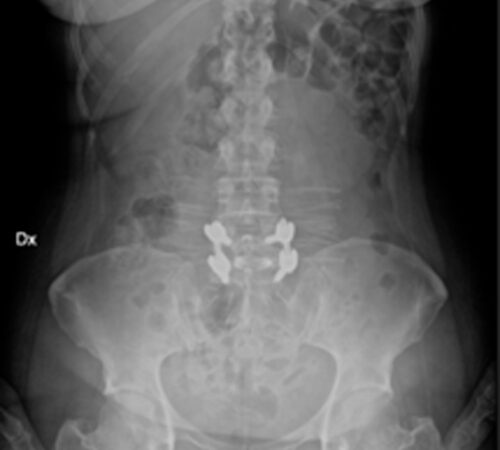

DIAGNOSI:

SPONDILOLISTESI CON STENOINSTABILITA’ L3-L5

Radiografia lombare pre-operatoria

Intervento chirurgico eseguito:

Artrodesi lombare mediante viti transpeducolari L3-L4-L5 + introduzione di cage intersomatica plif

Radiografia post-operatoria